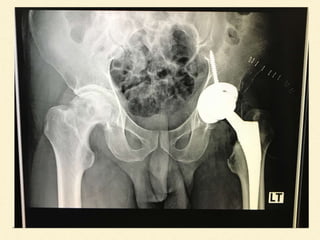

Film X-ray

Osteonecrosis of femoral head both

sides (More severe in Left side)

Set OR for left total hip replacement

DIAGNOSIS Osteonecrosis of femoralhead both sides (More severe in Left side)

TREATMENT Set OR forleft total hip replacement